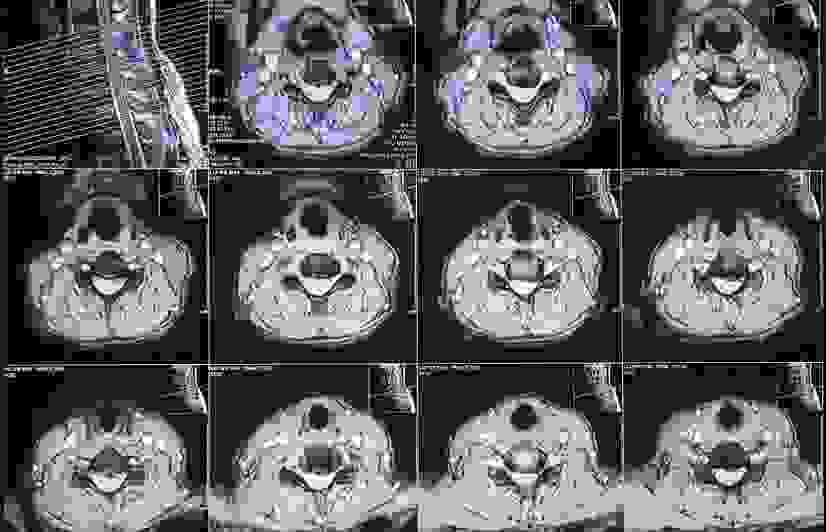

Sau 10 ngày điều trị cho ổn định sức khỏe và giảm tình trạng phù nề, bệnh nhân được chỉ định phẫu thuật lấy đĩa đệm, hàn xương liên thân đốt cổ lối trước (ACDF)